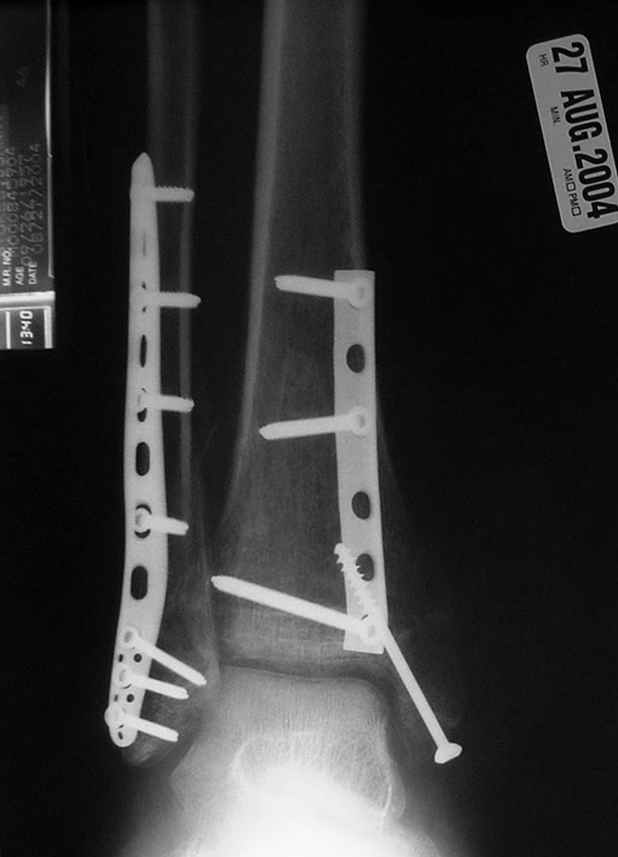

Второй случай сделан из одного разреза

ЕЧ LISS plate, mininvasive approach - luxurous !

На прямой проекции послеоперационного Рг макроскопически все выглядит очень анатомично, при микроскопическом ( :-)) ) рассмотрении можно все-таки заметить вальгизацию тарана, суставная щель в латеральном отделе сустава несколько уже , чем в медиальном при отсутствии латерального смещения тарана. У меня был аналогичный случай (без LISS , без мини доступа) с вальгусным наклоном тарана при восстановленном ankle mortise при последовательном наблюдении с интервалами в 6-8 недель в послеоперационном периоде отмечалось прогрессирующее сужение суставной щели в латеральном отделе сустава, закончившееся посттравматическим ОА, к счастью боли умеренные, купируемые аналгетиками или своими эндорфинами:-))(активная пациентка, у которой нет времени на болезни....) Какова жизненная ситуация в приведенном вами случае? И последнее, что я хотел бы прояснить для себя - фиксация внутренней лодыжки: я обычно комбинирую фиксацию компрессирующим винтом со спицей - по идее ротационная стабильность должна быть лучше, чем один винт, каковы ваши наблюдения в этом плане?